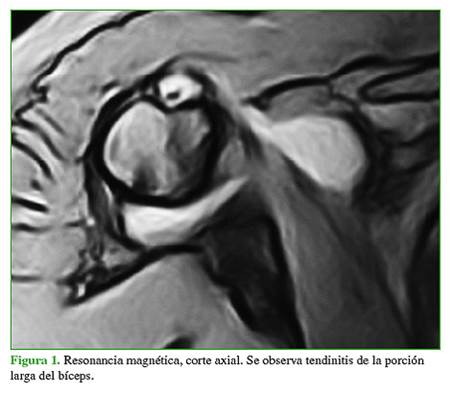

Además del aumento de líquido inflamatorio alrededor del tendón del bíceps, observado en las imágenes por resonancia magnética, el síntoma determinante para el diagnóstico y la inclusión fue el dolor en el surco bicipital acompañado de sensibilidad a la palpación durante el examen físico. Estos hallazgos, a menudo, estaban acompañados de una combinación de las pruebas de Yergason y compresión activa10 (Figura 1). A seis de los nueve pacientes se les había administrado una infiltración de corticoides como tratamiento sintomático, como mínimo tres meses antes de la cirugía, en todos los casos.